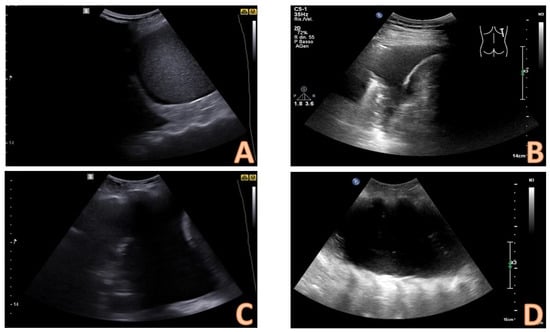

4. Ultrasound-Assisted Procedure

7. Ultrasound-Guided Thoracentesis